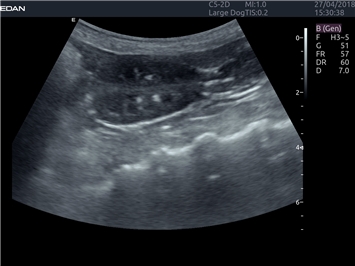

EDAN Acclarix LX4 VET

EDAN Acclarix LX4 VET представляет собой профессиональную ультразвуковую систему, специально разработанную для ветеринарных исследований. Сочетание стабильности, высокой производительности и эффективности делает эту систему идеальным выбором для современной ветеринарной практики.

• Оптимизация изображения для различных видов животных

• Улучшенная детализация структур

• Универсальные датчики для различных видов животных

• Специализированные предустановки для ветеринарных исследований